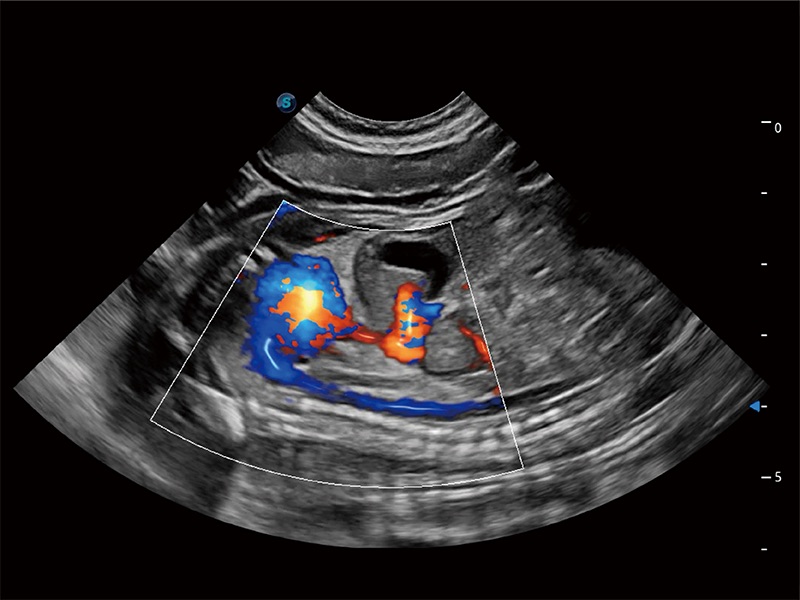

(犬)胎儿主动脉弓立体血流